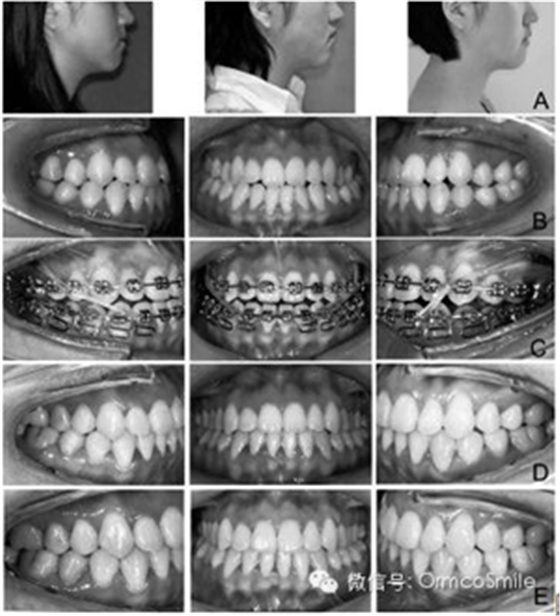

圖1 實驗組患者示例。

A 治療前、治療結束、保持一年后的側貌;

B 治療前口內像;

C 治療中口內像;

D治療結束時口內像;E保持一年后的口內像